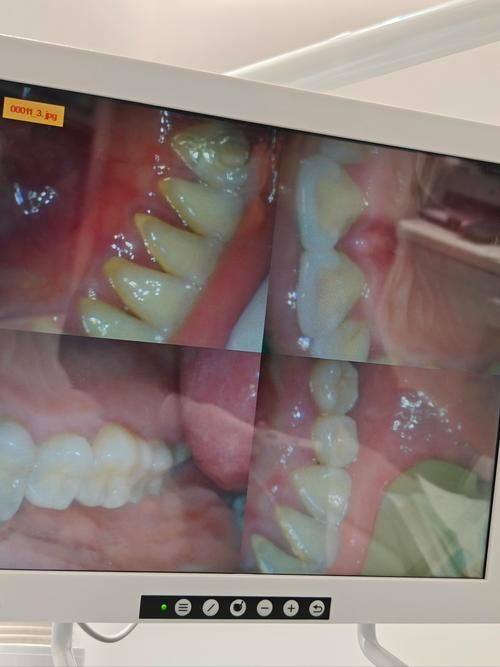

2. 口腔种植:诊所医生团队经验多,在种植牙齿方面技术成熟,为患者提供可靠的种植服务。

2. 我因为小时候不好好刷牙,好多牙齿都蛀了,只能拔牙后种植。在这家诊所种牙,医生技术特别娴熟,种植过程中没什么疼痛感。术后修复也良好,现在牙齿用着特别舒服,和自己原来的牙齿没什么区别。